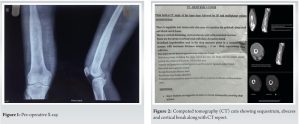

A 19-year-old male presents with a 6-month history of progressive pain and swelling in the left distal thigh, associated with difficulty in weight-bearing and walking. The pain is insidious, continuous, aggravated by activity, and relieved by rest. He reports intermittent fever and significant weight loss over the same period. There is history of knee aspiration done 6 months back for which medical records were not available. There is no history of trauma, tuberculosis, immunosuppression, or chronic illness. Clinical examination reveals localized swelling, warmth, broadening, irregularity, and tenderness over the distal femur, with restricted knee movement (10–40°) but preserved distal neurovascular status. Laboratory investigations show marked leukocytosis, significantly elevated ESR (130 mm/h), and C-reactive protein (15.9 mg/dL), indicating an ongoing inflammatory or infectious process. Mantoux test was also negative. The findings are suggestive of a chronic infective or inflammatory condition, such as subacute osteomyelitis or a neoplastic process, warranting further imaging and possible biopsy [3,4]. Radiological findings revealed an expansile lytic lesion with a wide zone of transition in the distal femur, cortical thickening and sclerosis, solid periosteal reaction, areas of cortical break with cloaca formation, and ill-defined soft tissue fluid collection-suggestive of acute on chronic osteomyelitis [5] (Fig. 1).

Computed tomography imaging confirmed the presence of sequestrum, abscess formation, and cortical break, correlating with the radiographic findings (Fig. 2 and 3).